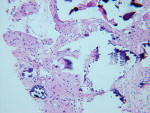

Postimplant Histological Assessment

BSEM and histological evaluation of Puros and Bio-Oss biopsies at Progentix laboratory 9 months after socket bone grafting and 6 months after implant insertion showed similar levels of new bone formation in both Puros and Bio-Oss sites. However, in the Bio-Oss biopsy, granules remained at the site, which were surrounded mostly by fibrous tissue and isolated from the newly formed bone (Figure 8); in the Puros biopsy, the newly formed bone was distributed evenly and there were no signs of remaining granules (Figure 9).